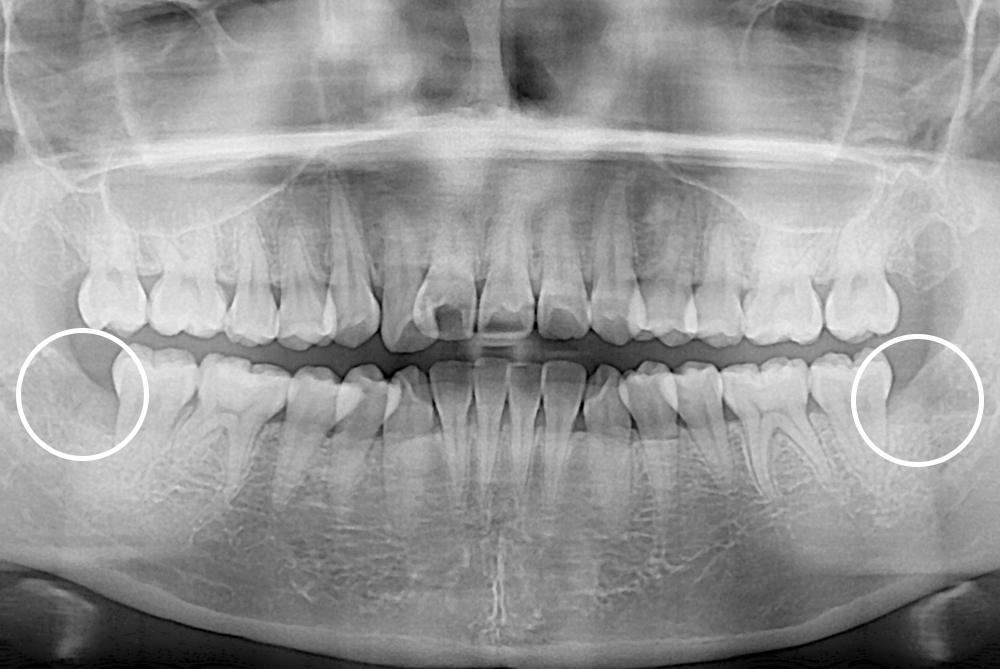

[사랑니] 매복 사랑니 발치

치료후 : 2018-05-31

세종치과는 구강악안면외과학 박사이신 원장님이 발치하는 치과입니다.